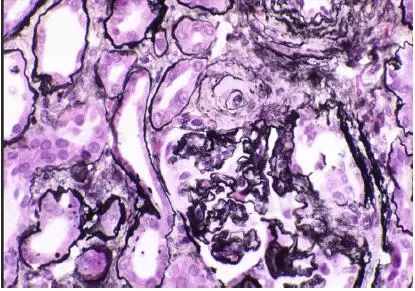

CNI肾毒性导致的血管收缩无形态学变化。急性CNI肾毒性特征包括:近端肾小管上皮细胞空泡化,大小一致;血管损伤,平滑肌细胞丢失;肌细胞胞浆空泡化;细胞坏死或凋亡退化。肌细胞损伤最终发展为局灶性结节性玻璃样变和透明样变,可延伸至小动脉和动脉血管壁整个中层。CNI肾毒性还可引起血栓性微血管病变(TMA),主要累及小动脉和肾小球毛细血管袢。慢性CNI毒性特征为:条状间质纤维化,肾小管萎缩。

图3 CNI肾毒性透明样变延伸至动脉中层和节段性肾小球硬化(Jones 银染)